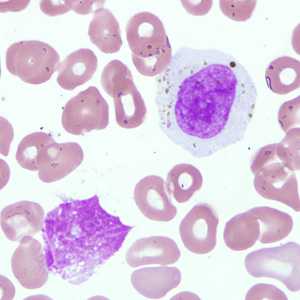

A 45-year-old immigrant from Mexico was admitted to the hospital after experiencing headaches, fever, pulmonary symptoms, and adenopathy. Because of his travel history, a blood specimen was collected and sent to Hematology for routine work-up, including blood parasitology.

November - 2008 - Case #239